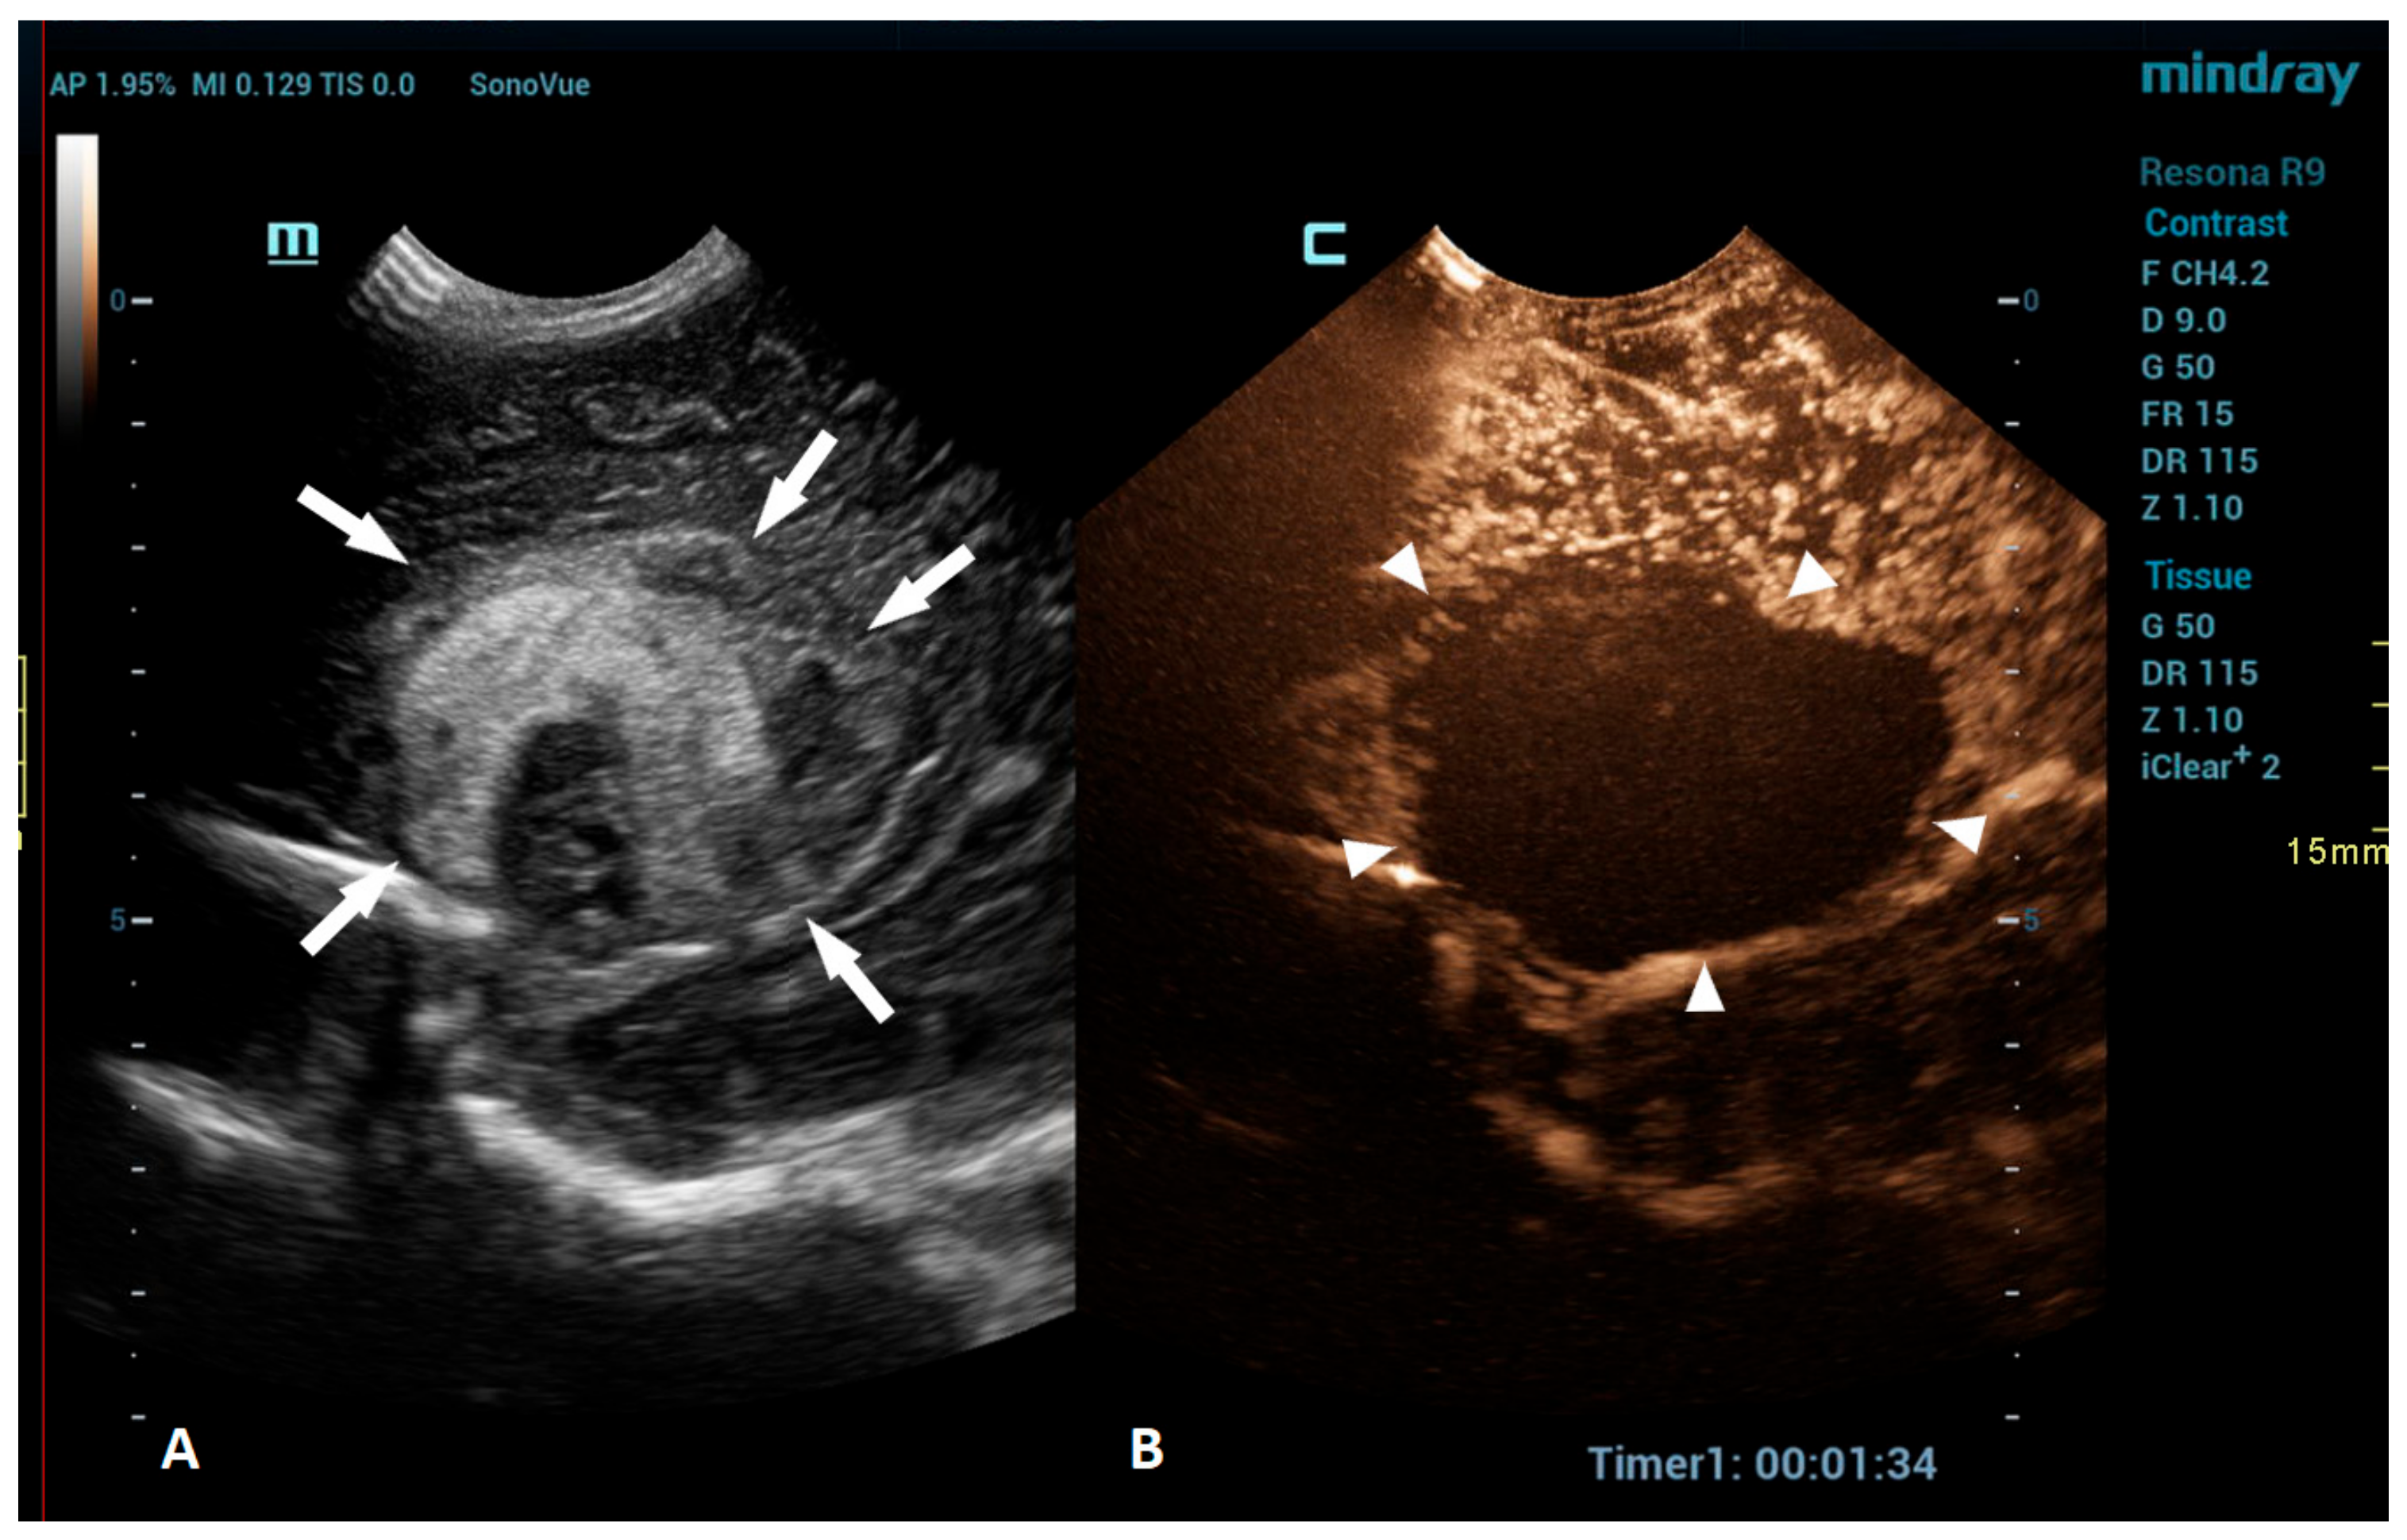

CEUSs can also be a great problem-solving tool in the assessment of brain vasculature, especially the evaluation of brain sinuses for the presence of thrombosis. Due to the slow flow in the brain sinuses, MRI can be unreliable in diagnosing sinus thrombosis [74]. CEUSs using an approach through the anterior fontanelle enables a good visualization of the sagittal sinus, while the transtemporal and transmastoid approaches provide a great visualization of the transverse sinuses (Figure 5).

Figure 5.

A 5-day-old boy diagnosed with hypoxic-ischemic encephalopathy was investigated for suspected thrombosis of the right transverse sinus (suspected on MRI scan). (A) The transverse reference grayscale ultrasound image through the right mastoid fontanelle and increased echogenicity within the transverse sinus (arrow). (B) The CEUS image of the right transverse sinus shows the sinus with high signal intensity (arrow), ruling out thrombosis.